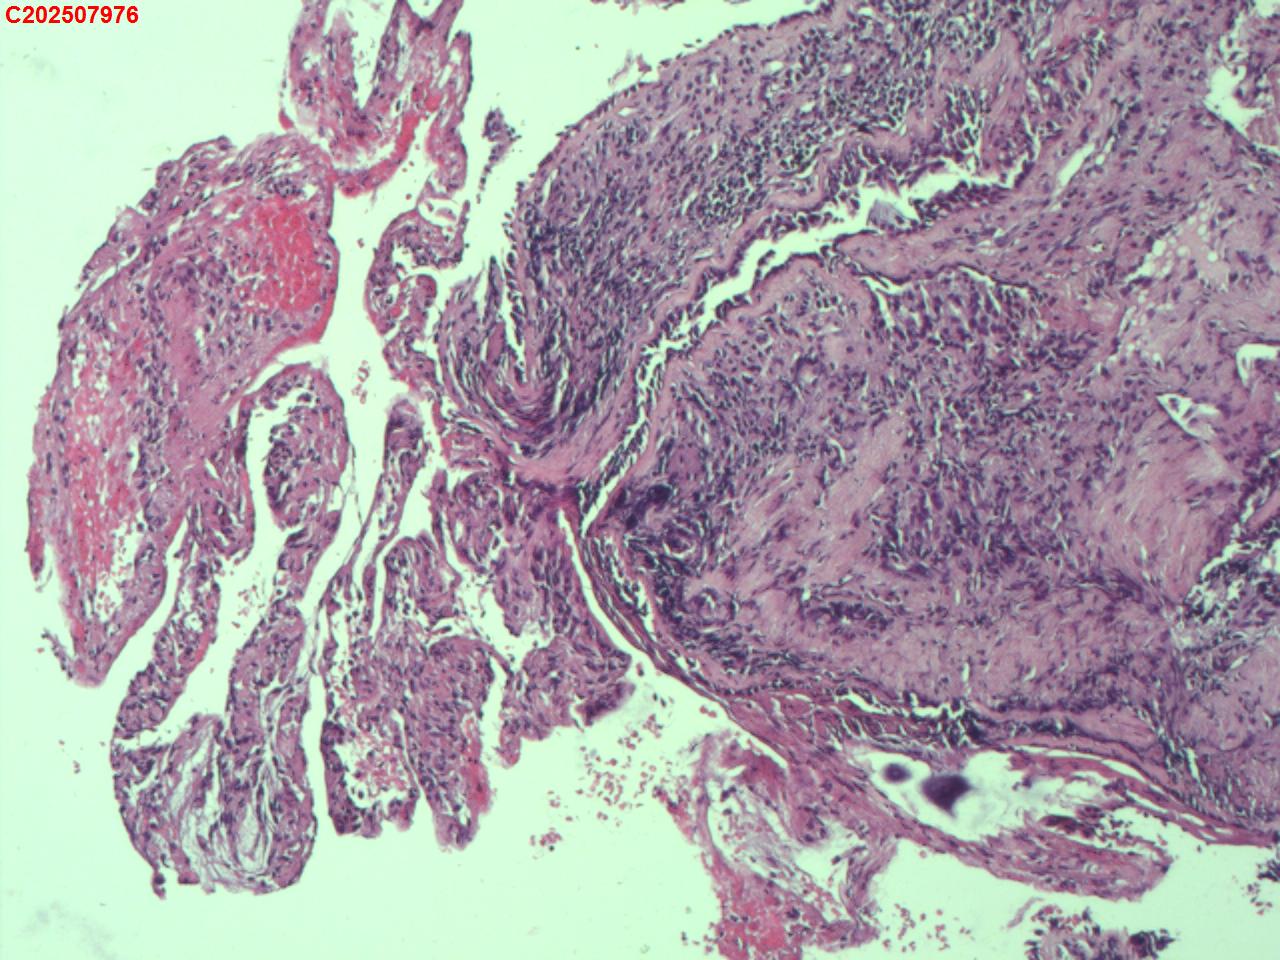

右肺上叶开口处 气管镜咬检

右肺上叶开口上缘处可见肉芽增生,予咬检。

感觉:炎性纤维组织增生